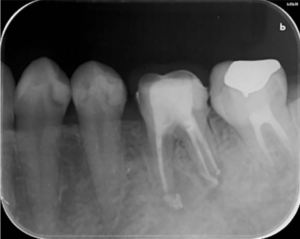

歯の根の治療中のレントゲン写真です。

歯の根の中を清掃する器具を入れています。根の中のばい菌を除去してきれいにしています。

歯の根の中を清掃し終わった後に内部に薬を詰めた直後のレントゲン写真です。

薬は根の中に緊密に詰まっています。一部先から漏れている部分もありますが、のちに吸収されていきます。